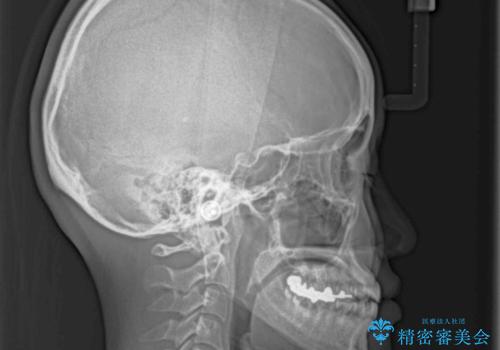

- 前歯のデコボコを治したいとのことで来院された患者様です。

下顎が前方位にある方であったため、下顎の歯列全体の後方移動とIPR(歯と歯の間を削る)によってデコボコが解消するように設計し、インビザラインにより治療を行うこととしました。